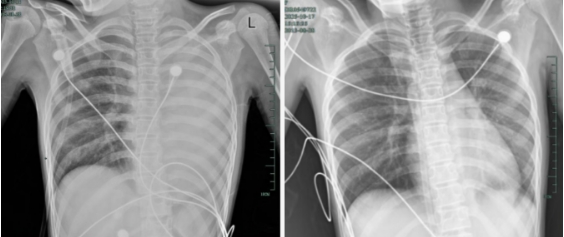

治疗前后影响对比,左肺从“白肺”到正常状态。

呼吸急促、胸闷胸痛,体温38.5℃,只能靠 5L/min 的面罩吸氧维持血氧,胸片显示左肺已完全呈 “白肺” 改变,肺部炎症进展迅猛。